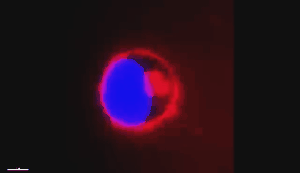

这张图就是这套系统拍摄的人体上皮细胞的三维图,这是这套系统拍摄的肝癌活细胞在肝癌靶向药物的作用下被杀死的过程。

人体上皮细胞三维成像

蓝色的是细胞核,外边一圈粉色的是细胞膜外包裹的药物。这个药物进入到细胞里,然后把细胞杀死了。

靶向药物作用肝癌细胞

有了这样的系统,我们很高兴,因为它可以加速我国肝癌靶向药物的研发进度,让更多的癌症患者得到及时的治疗和康复。